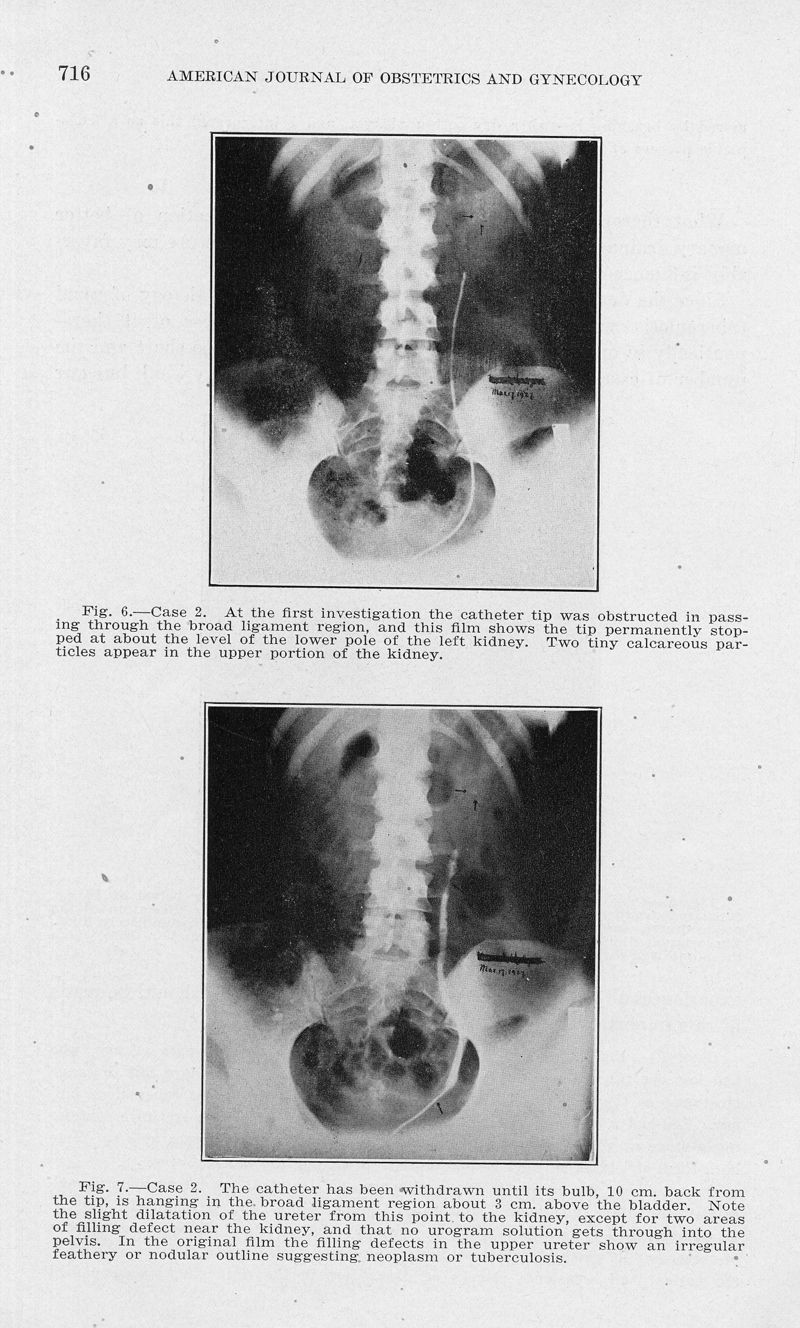

Consideration of a new viewpoint on the etiology of renal tuberculosis in women

In : American journal of obstetrics and gynecology, 1932, Vol. 24, pp. 706-28